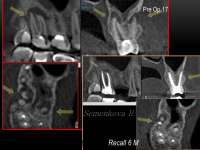

14732846429870.jpg (43Кб, 741x273)

14732846429881.jpg (214Кб, 1280x720)

Как и обещал. Забавно, в зеркале кажется не так криво.

Боль на третий день похожа на второй день, спасаюсь болеутоляющим. Но целом уже привык.

Вчера делал панорамный снимок. Всё как >>513480 сказал, ортодонт взял его только посмотреть. Внимание, вопрос знатокам, ортодонт посмотрел на второй пикрелейтед и сказал, что зуб в котором штифт нужно переделывать - канал не полностью залечили, а так же второй зуб - там тоже проблема с каналом и что если ставить брекеты, то им обоим придет пизда. Когда это лечить не понятно, времени в обрез, завтра пойду к своему врачу который год-полтора назад мне эти зубы лечил, послушаю что скажет. В то, что она плохо сделала не хочется верить, но нужно быть реалистом.

Еще вопрос, сегодня пидорю зубы и вижу ДЫРУ, ЧЕРТОВУ ДЫРУ В ДЕСНЕ около места, из которого мне выпилили зуб мудрости. Еще вчера этой дырки не было, засунул туда ершик, дырка оказалась глубокая, вытащил оттуда петрушку, попутно отложив немало так кирпичей. Завтра побегу к хирургу. Всё это уже знатно так заебало, за лето потратил на брекеты, пломбы, снимки, лекарства и прочие операции больше 40к и конца этому не видно.

>>514182

Да, надо перелечивать тот что левый (без штифта). Там Уже процесс в области верхушки корня есть как мне кажется, а то что я прав 99.9999% , а тот что со штифтом надо вообще посмотреть на прицельном снимке. Мне он не очень нравится.

1- дыра будет затягиваться достаточно долго. но нет,ты не будешь ходить год с отверстием. Десна затянется + там уже начнет образовываться кость. Нормальной структуры она будет только через месяцев 6 и чуть более. Но дырка закроется много раньше. не ссы.

2- НЕ СУЙ НИЧЕГО В ЭТУ ДЫРКУ! НЕ ВЫЧИЩАЙ ОТ ТУДА КРОВЬ, И БЕЛУЮ ФИБРИНОВУЮ ПЛЕНКУ! НЕ ЖУЙ НА ТОЙ СТОРОНЕ ПАРУ НЕДЕЛЬ ПОСЛЕ УДАЛЕНИЯ будешь нарушать этуй хуйню - удалишь сгусток и мало того , что нарушишь заживление, то еще и воспаление начнется. Будет тупо болеть. Потом доктору придется опять скрести у тебя в дырке -собирать кровяной сгусток + принимать вещества